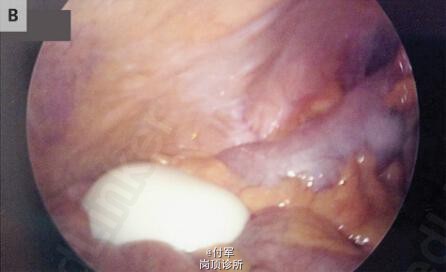

体格检查和实验室检查无异常。腹部和骨盆CT显示有一个直径为8.5cm长的肿块,伴有中心钙化(图A,红色箭头),在膀胱上方并压迫膀胱(图A,蓝色箭头)。 腹腔镜探查显示一个游离、光滑、坚硬且有弹性,10cm×9.5cm×7.5cm,重220克的肿块(图B和图C)。 切片标本包含多层,绿色墨水用来描绘切片边缘(D图)。组织学上,该肿块主要包含非细胞、分层的纤维组织,标本中心包含蛋白样组织伴有纤维样坏死,周围一圈钙化。